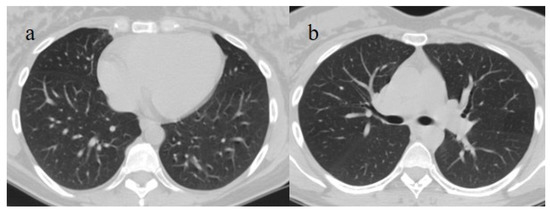

3.1. COVID-19 Pneumonia: Role of Chest CT and Chest Features from the Wild-Type to the Omicron Variant

| Typical Appearance | GGOs with a crazy-paving pattern and consolidations in a peripheral and posterior or central-peripheral distribution; multilobar involvement; vascular enlargement, the halo and reversed halo sign; subpleural and parenchymal bands; and architectural distortion. They were predominant since the Delta wave. |

| Atypical Appearance | Lobar consolidation, lung nodules or masses, miliary patterns, tree-in-bud patterns, cavitation, pleural effusion, central distribution, and lymphadenopathy. Atypical appearances were predominant during the Omicron waves. |

| Typical appearance | From the wild-type to the Delta variant. | Askani et al., 2022 [67] | The Delta variant presented more frequent typical features with more extensive lung involvement than the Omicron variant. The Omicron variant was more frequently associated with the absence of pneumonia. |

| Kirka et al., 2022 [27] | Typical features were found in 40.8% of patients with the wild-type variant and 1.7% of patients with the Omicron variant. | ||

| Lee et al., 2023 [28] | Typical CT patterns were more frequent in the Delta group (76%) than in those with the Omicron variant (42%). | ||

| Yoon et al., 2023 [69] | Only 32% of patients with the Omicron variant presented typical findings, compared with 57% of the Delta variant cases. | ||